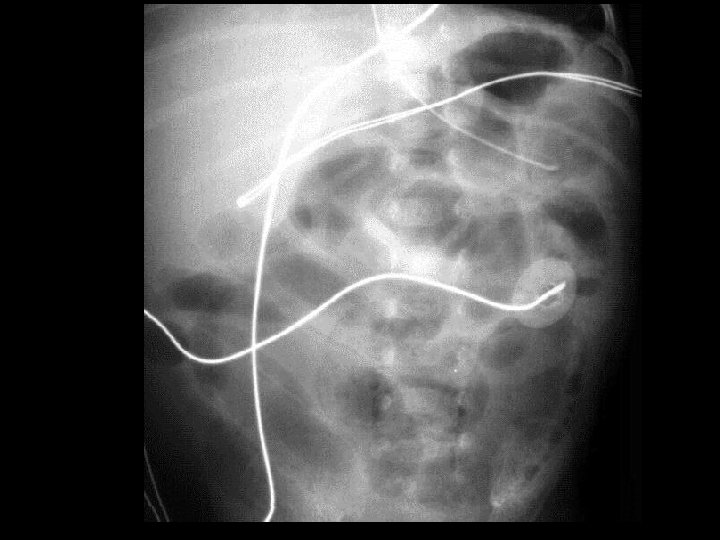

Case 2 Radiology Evaluation • Upper GI – Flow through normal duodenum, duodenal-jejunal junction, jejunum • Contrast enema – Microcolon – Distended RUQ loops do not fill during enema • Small bowel follow-through – Opacification of distended loops Jose Chavez CHO MR 960117

Case 2 Radiology Diagnosis • Microcolon • Dilated ileum secondary to obstruction • Differential diagnosis: – Stricture – Adhesions – Meconium Ileus Jose Chavez CHO MR 960117